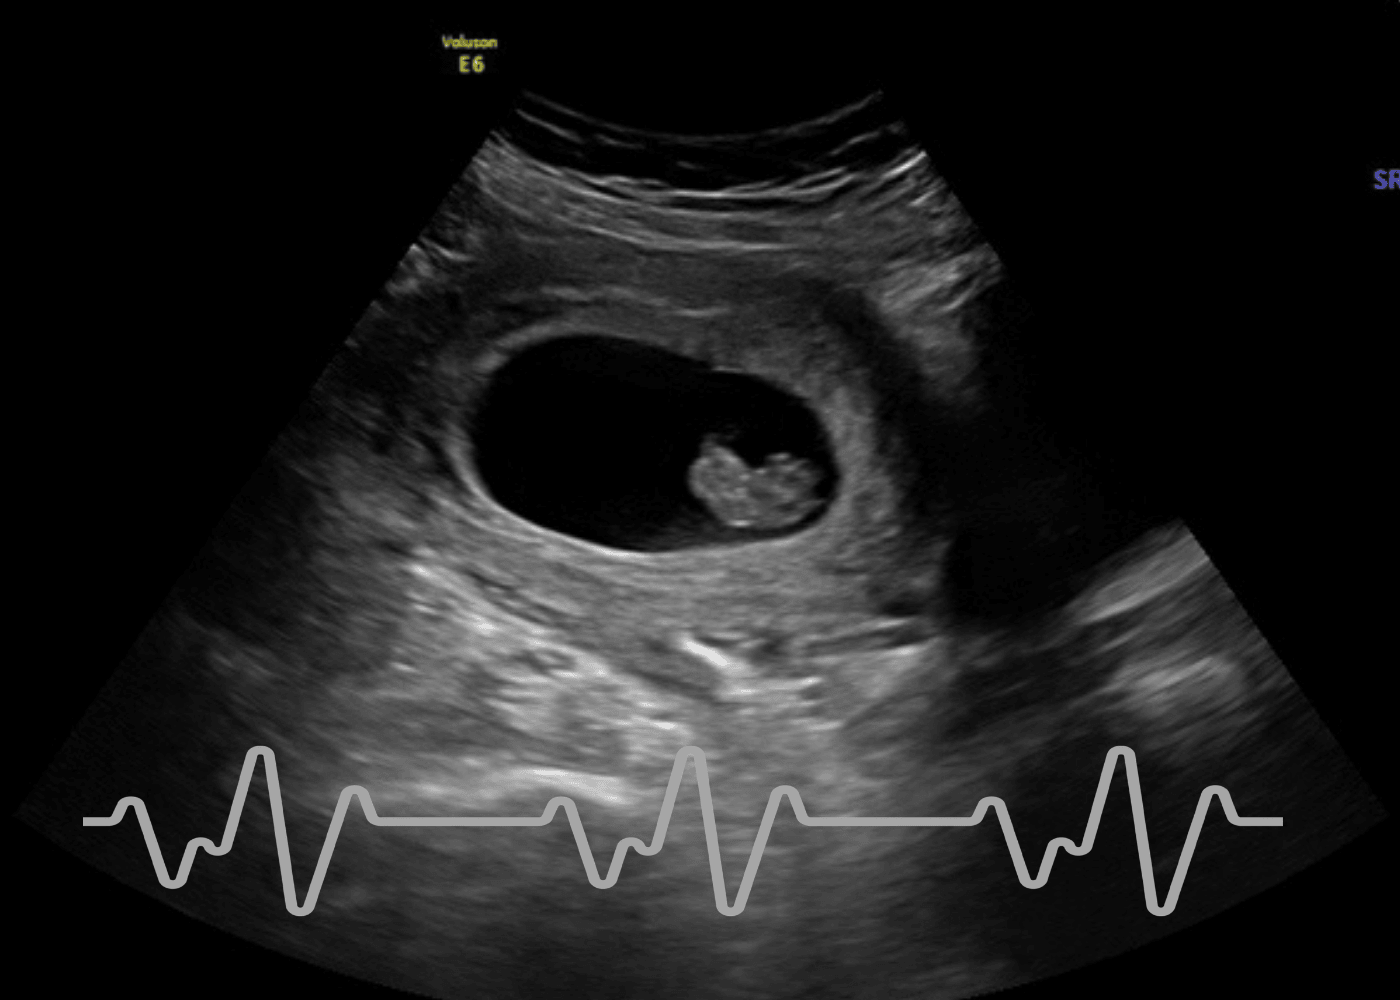

Ultrasound image of an early pregnancy showing a gestational sac with an embryonic heartbeat, with a heart rate monitor line overlay.

Ultrasound scan of a developing fetus in the womb, with a heartbeat waveform displayed at the bottom.

6–10 Weeks

Early Reassurance $75

A gentle, focused visit designed to confirm baby’s heartbeat during the earliest weeks of pregnancy.